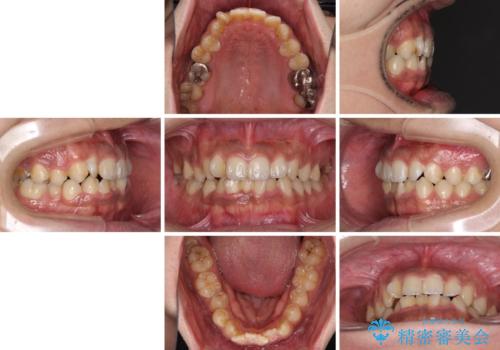

- 前歯のデコボコを気にして来院された患者様です。

前歯が90度近く捻れていたため、しっかりと治すことを考えるとワイヤー矯正の方がおすすめではありましたが、本人の希望によりインビザラインを用いて矯正治療を行うこととしました。

インビザラインは、十分な装着時間が達成されると前歯のデコボコをしっかりと改善できますが、1日の装着時間が20時間に達しなくなると、不十分な仕上がりとなるため、しっかりと装着するよう指示をしました。